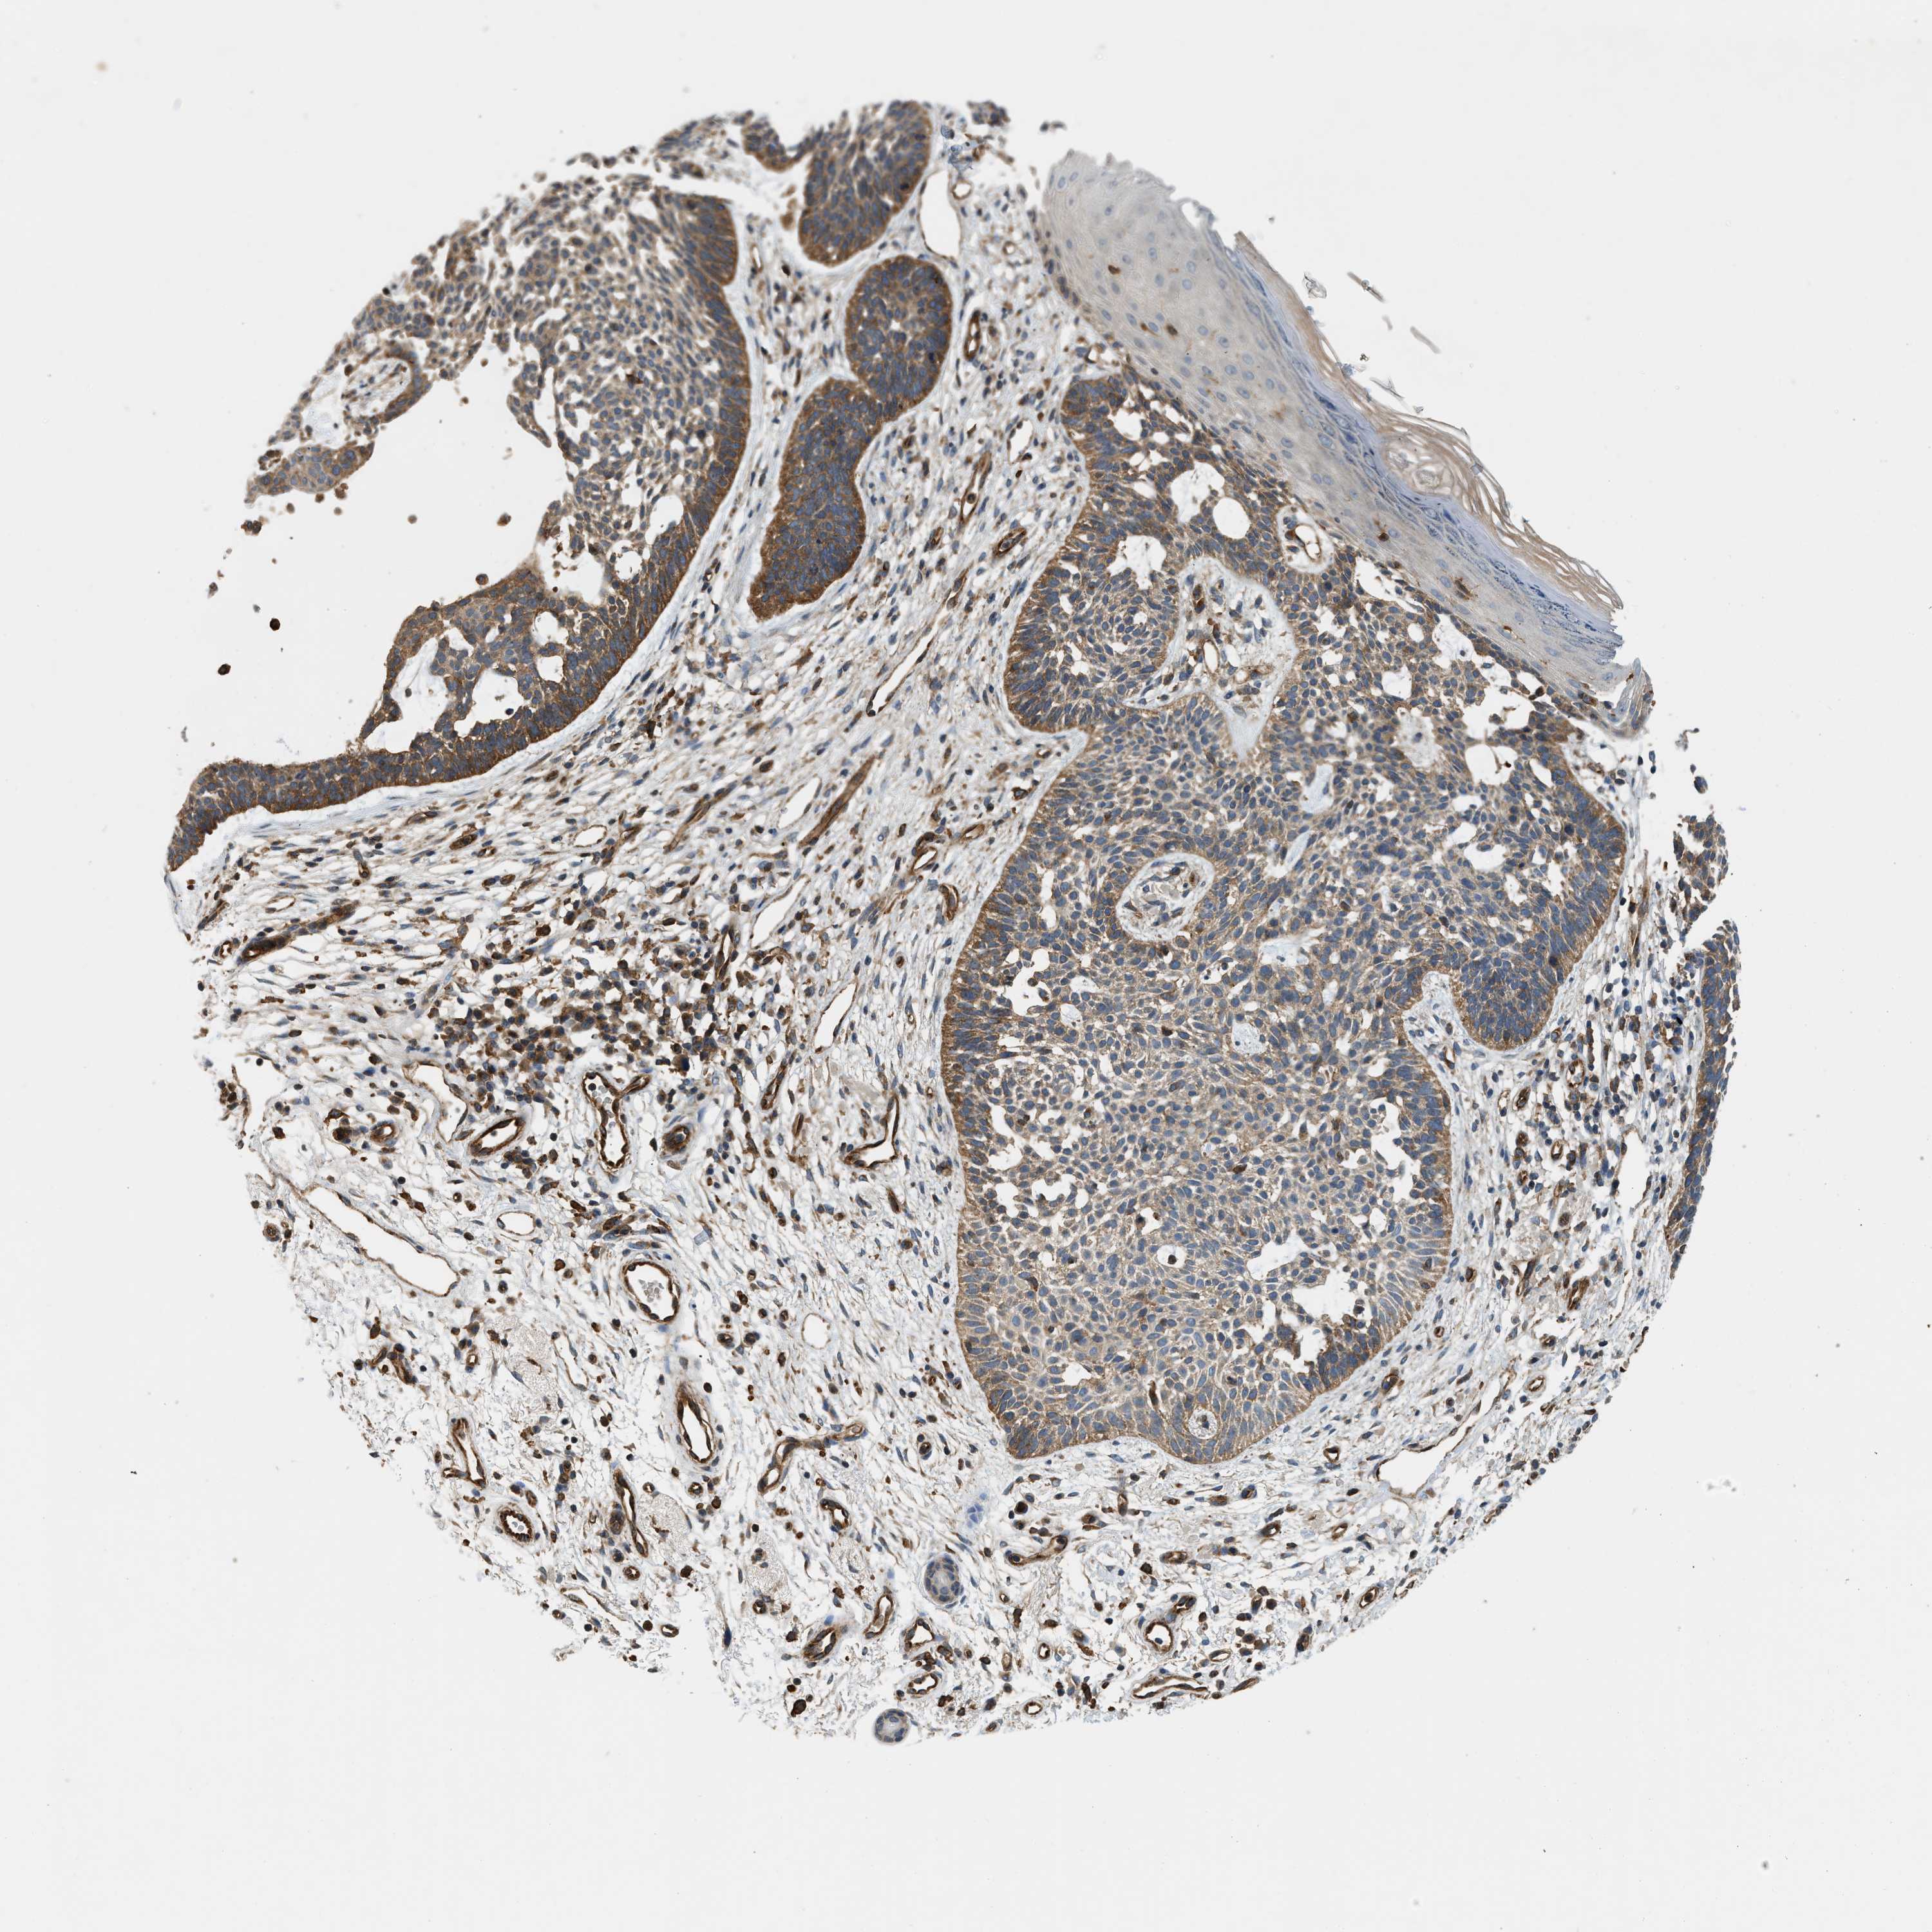

SKIN CANCER - Protein expressioni

A mouse-over function shows sample information and annotation data. Click on an image to view it in a full screen mode. Samples can be filtered based on level of antibody staining by selecting one or several of the following categories: high, medium, low and not detected. The assay and annotation is described here.

Antibody stainingi

Antibody staining in the annotated cell types in the current human tissue is reported as not detected, low, medium, or high, based on conventional immunohistochemistry profiling in selected tissues. This score is based on the combination of the staining intensity and fraction of stained cells.

Each image is clickable and will lead to virtual microscopy that enables deeper exploration of all samples and also displays staining intensity scores, fraction scores and subcellular localization as well as patient and tissue information for each sample.

Antibody HPA017964

Staining

High

Medium

Low

Not detected

Intensity

Strong

Moderate

Weak

Negative

Quantity

>75%

75%-25%

<25%

None

Location

Nuclear

Cytoplasmic/membranous

Cytoplasmic/membranous,nuclear

Squamous cell carcinoma, NOS

Basal cell carcinoma